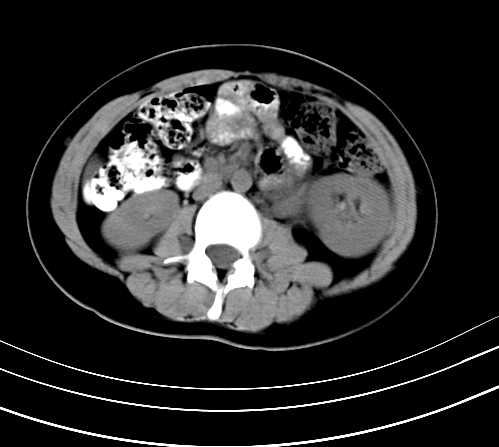

腹部平扫

静脉期